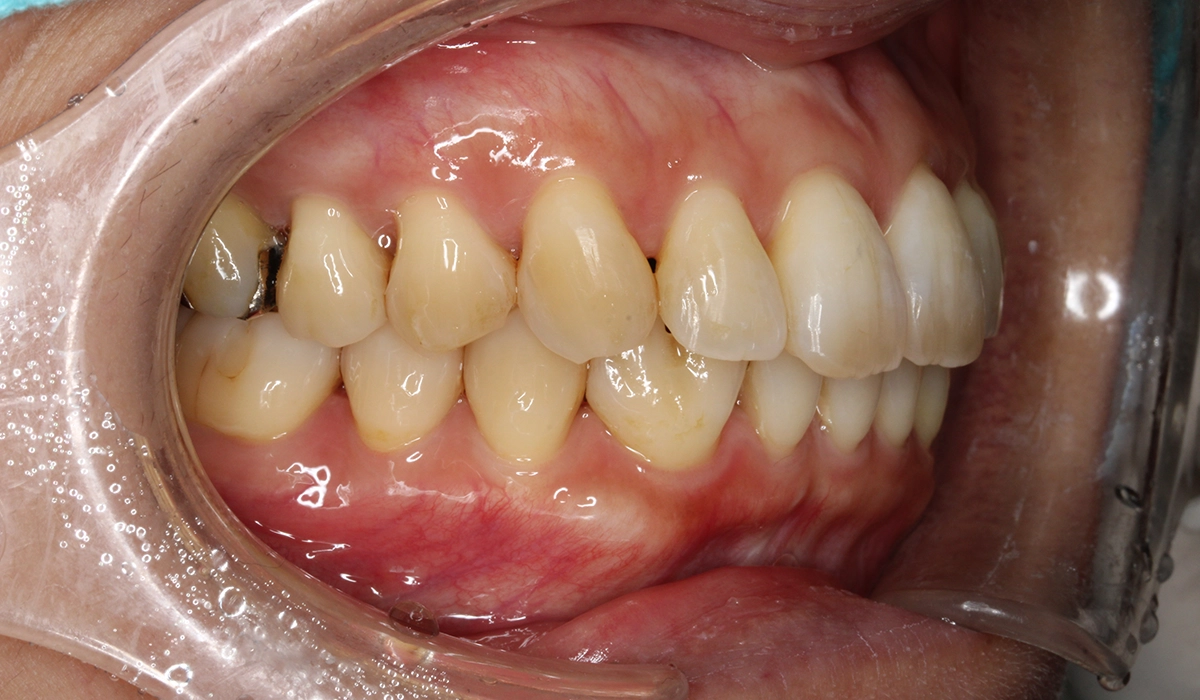

術前:右側

術後:右側